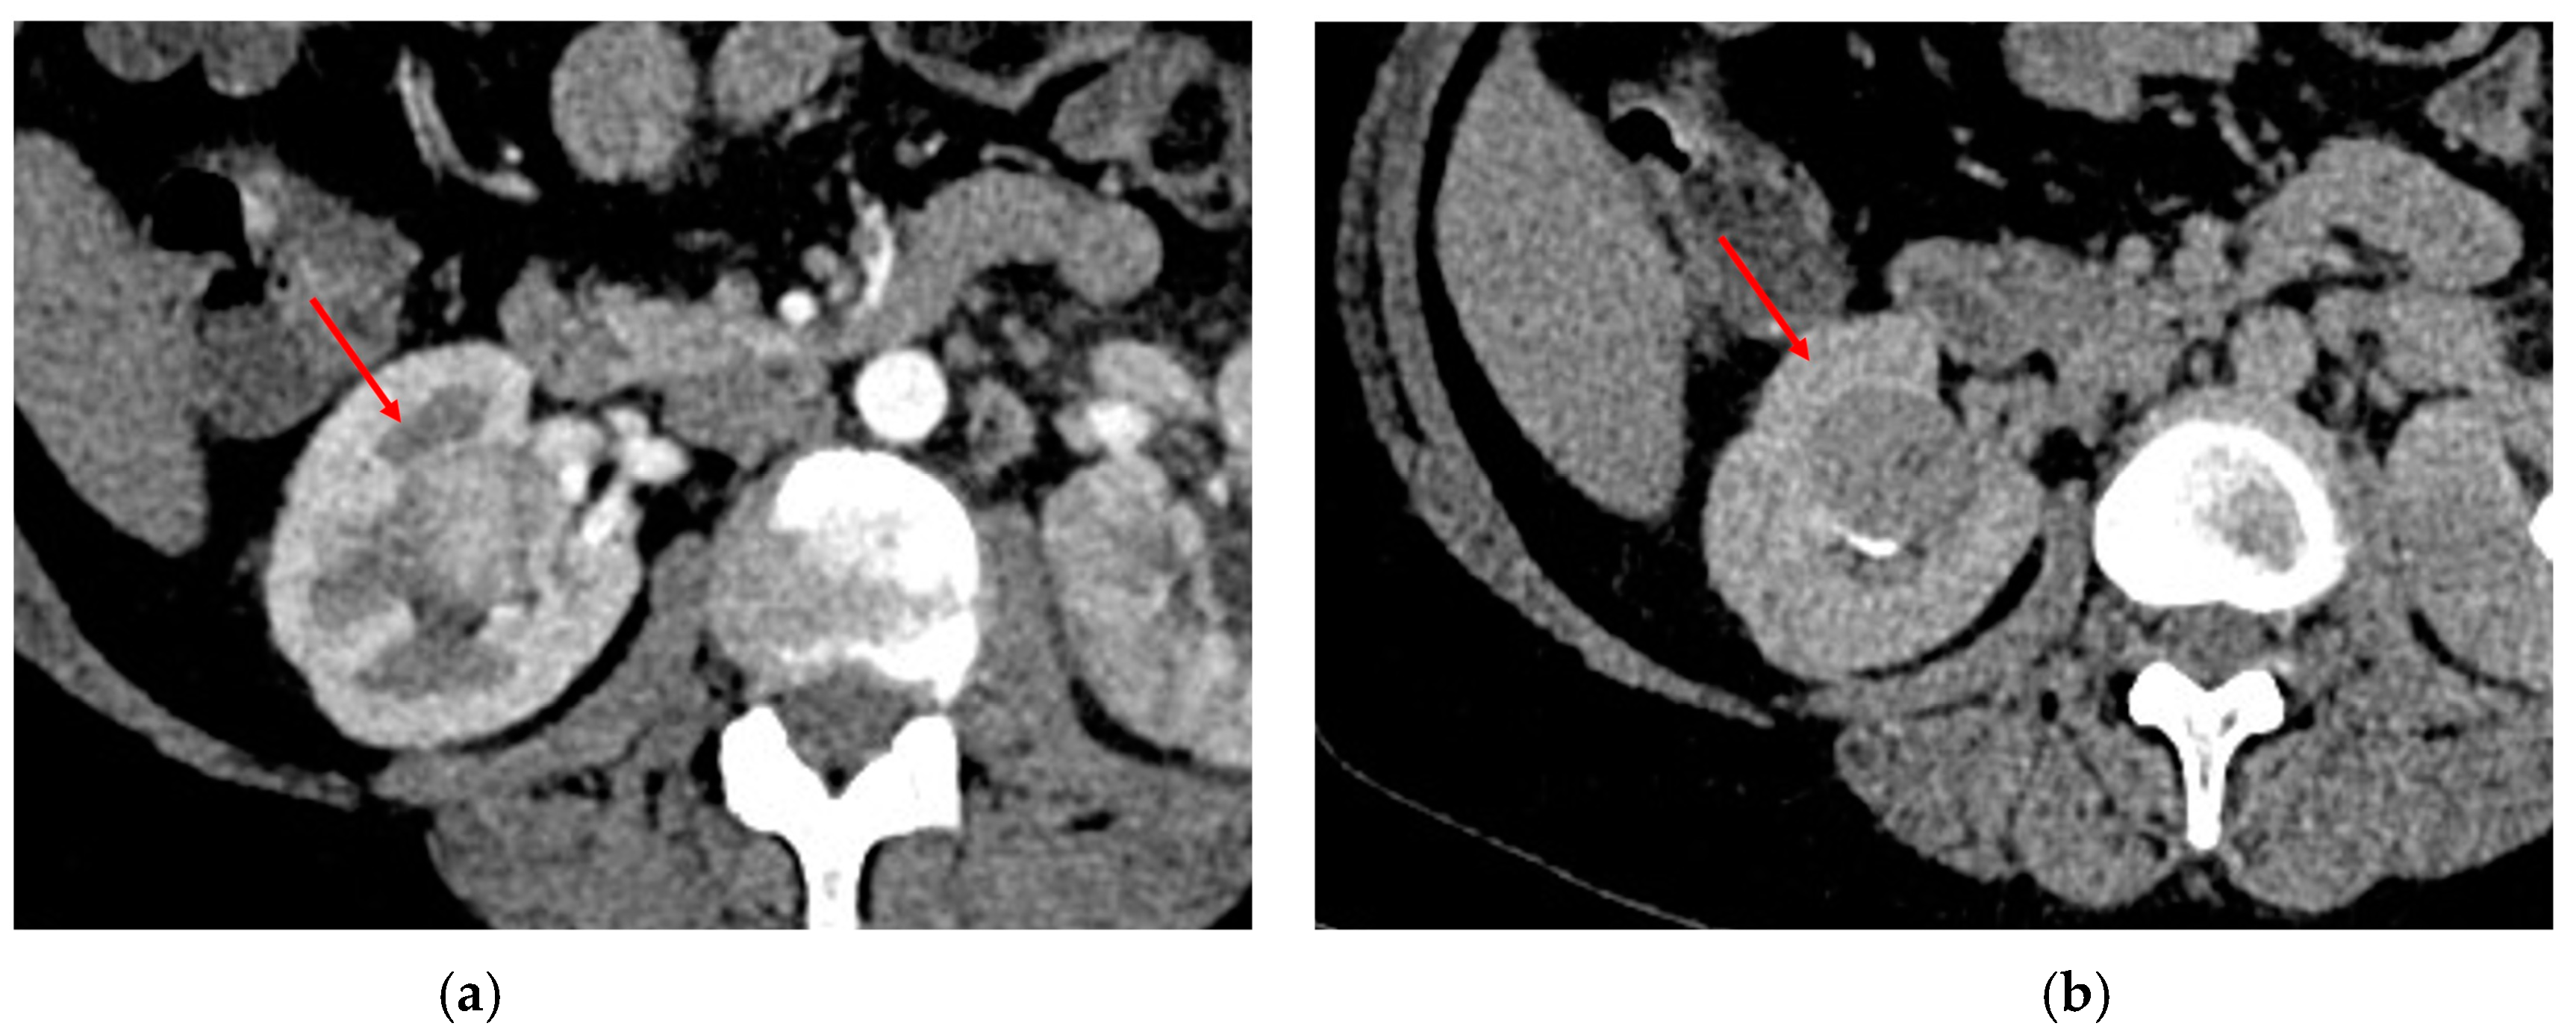

3.2. Papillary RCC